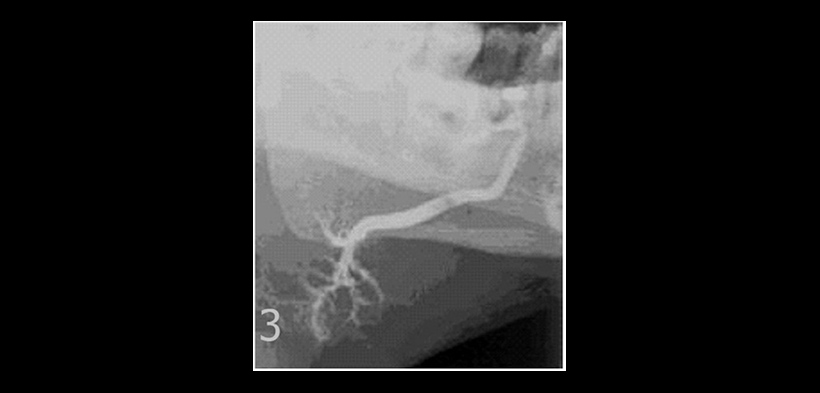

Fig. 3. Sialografía convencional del mismo caso anterior, vista lateral, reveló una imagen hipodensa compatible con un sialolito, visto dentro del conducto principal que ocasiona la dilatación de la glándula submandibular izquierda, y la dilatación de los conductos secundarios y terciarios.